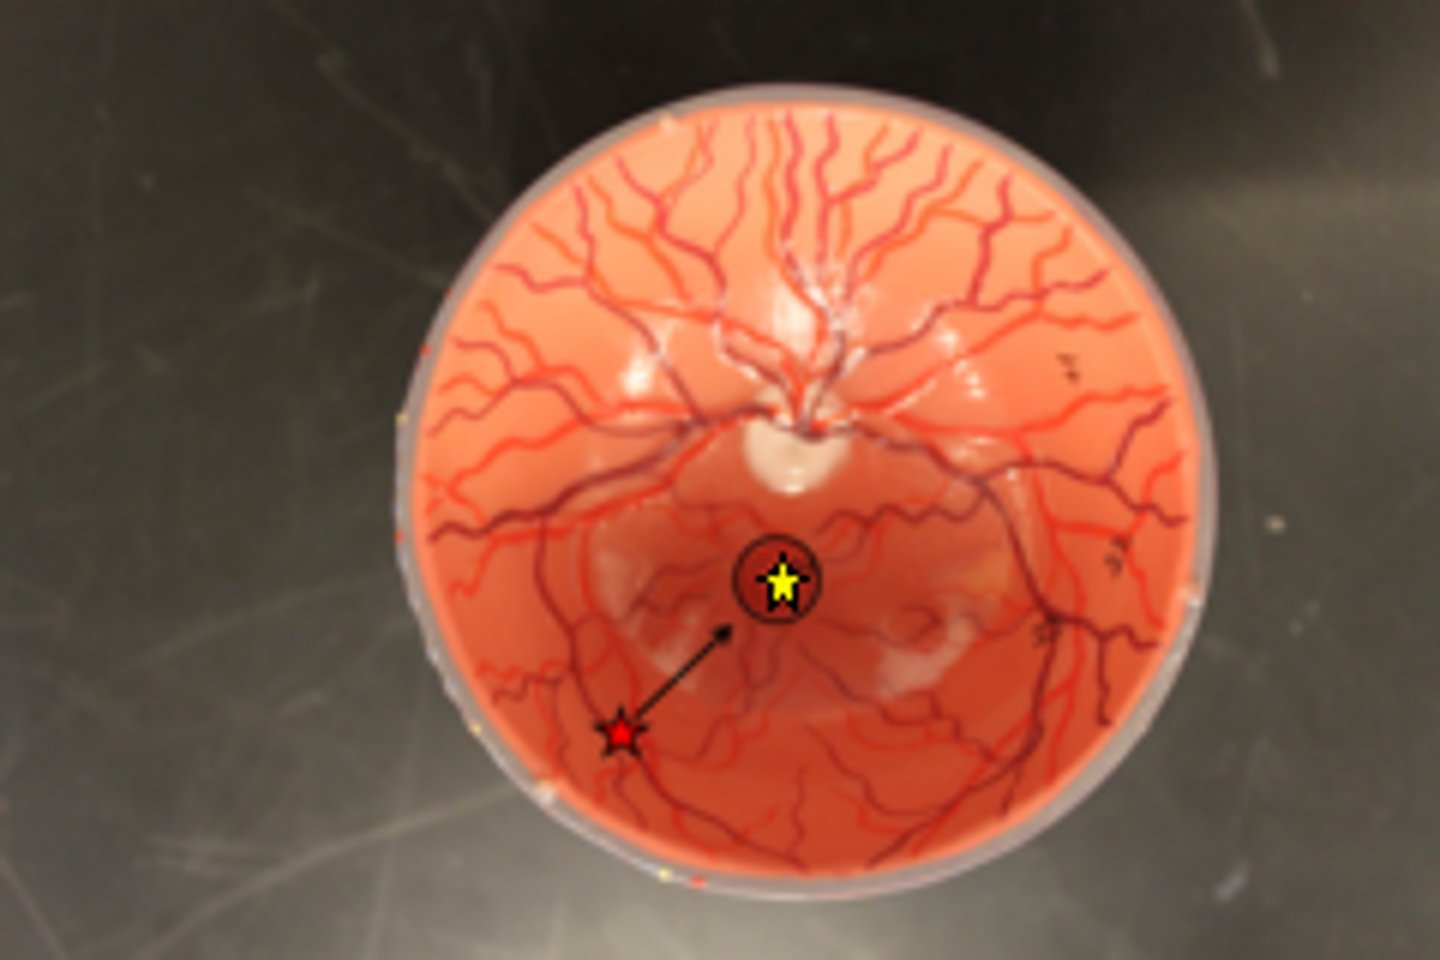

optic disc

choroid coat

name 1

tapetum lucidum

macula lutea

fovea centralis